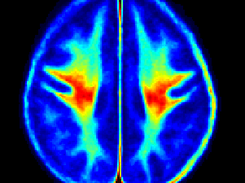

Normative myelin water atlas was created by co-registering and averaging myelin images in MNI space from 50 healthy brains to depict the population mean and variability of the myelin content in the brain. The myelin images of individual subjects were acquired using myelin water imaging. Details about myelin water imaging technique and its analysis can be found here: https://mriresearch.med.ubc.ca/news-projects/myelin-water-fraction/. The created myelin water atlas with its standard deviation can be used as a reference for your own studies related to myelin. A full description of this work can be found in this paper: https://www.ncbi.nlm.nih.gov/pubmed/31347238.

• Myelin water imaging

• Atlas for normal myelin content